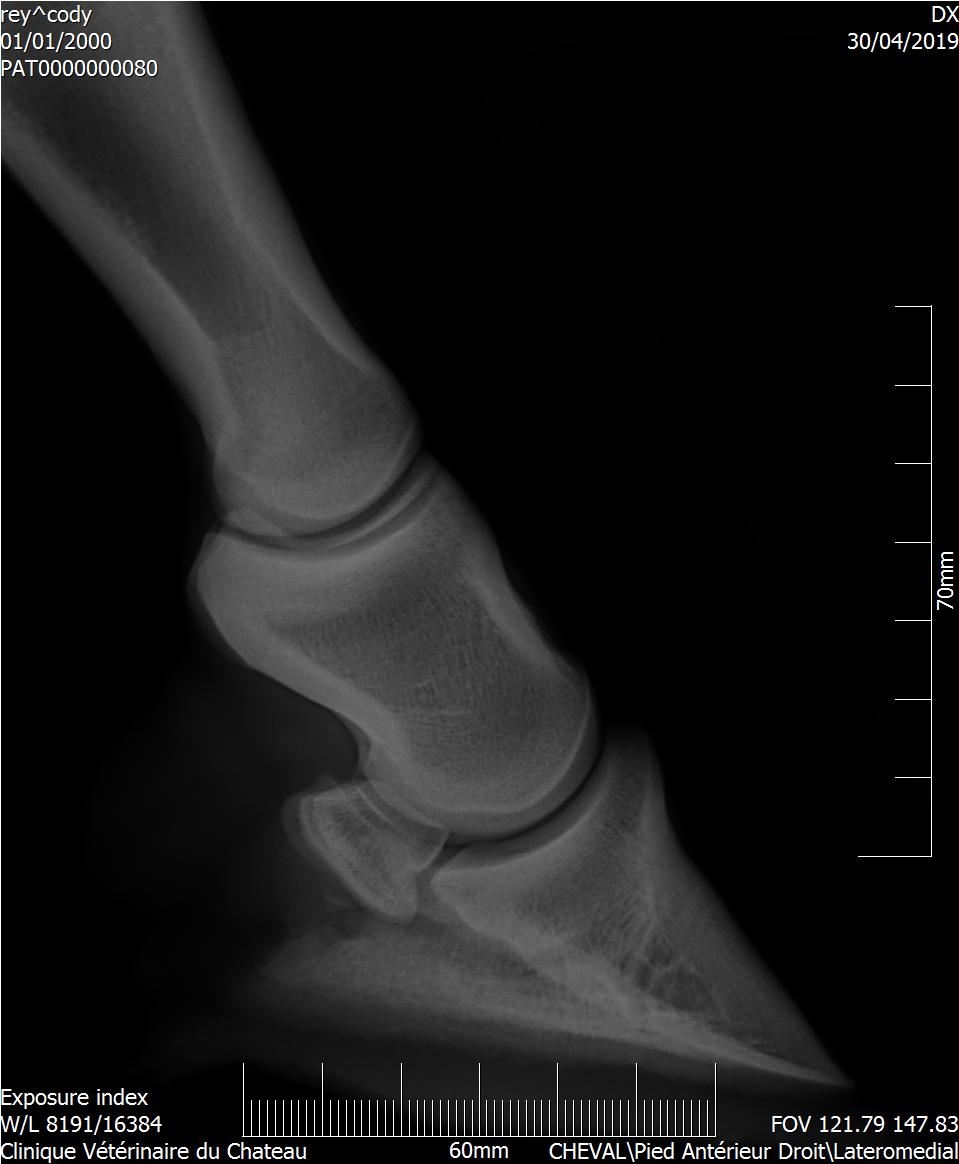

| Dire merci | Les radios ont été faites hier, il y a clairement un souci sur le naviculaire antérieur droit (le véto m'a montré le cliché sur l'écran). |

| Dire merci | Dès que j'ai les radios je ferai le point avec le véto. Il a effectivement parlé d'un tendon qui viendrait frotter sur l'os et sur la nécessité d'adapter le parage. La boiterie est très légère, et ne permet pas de faire le test en anesthésiant une partie du pied. |

| Dire merci | Dans le cas que je connais bien, l'os naviculaire est en sale état. Mais la douleur et donc la boiterie, vient du tendon qui s'enflamme en frottant sur cet os "rugueux" (je ne connais pas le terme exact). Donc avec un parage adapté, un pré plat (très important), peu de travail et surtout éviter le galop (je parle toujours du cas de Kachou) ainsi que tout travail en cercle, on peut donner du confort au cheval. Mais il n'est pas guéri, hélas, et il suffit de peu de choses pour qu'on le voie à nouveau boiter. |

| Dire merci | Voici le compte-rendu du véto : Examen général: L’examen locomoteur au pas et au trot en ligne droite ne met pas en évidence de boiterie. Le cheval pose l’antérieur droit en deux temps : pose d’abord en muraille externe puis en interne. Une boiterie 2/5 de l’antérieur gauche apparait sur le cercle au trot à droite Examens complémentaires : Radiographie : Pieds de face : 3-4 fossettes synoviales sur le bord distal du naviculaire antérieur droit, de profondeur faibles et peu ouvertes. 2-3 fossettes synoviales dont l’une plus ouverte sur le bord distal du naviculaire antérieur gauche Léger pincement articulaire p1-p2 et p2-p3 coté externe visible sur le membre à l’appui. Boulet de face : Petit remaniement osseux au niveau de l’insertion proximale du ligt coll int Boulet et pieds ant droit de profil : ras La boiterie étant trop légère pour préciser la localisation par anesthésie étagée, plusieurs hypothèses sont envisagées. Par ordre d’importance : • Pincement et fatigue articulaire lié au parage ou à une compensation d’une légère entorse boulet • Entorse du boulet • Début syndrome podotrochléaire Message édité le 14/05/19 à 18:37 |